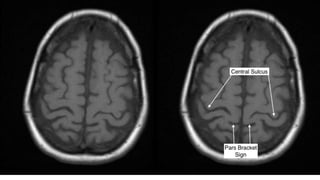

The central sulcus-The sigmoid hook

The pars bracket sign- Parieto occipital sulcus

Fish tail- parieto occipital sulcus

Pars marginalis

The bifid sulcus

The intraparietal sulcus